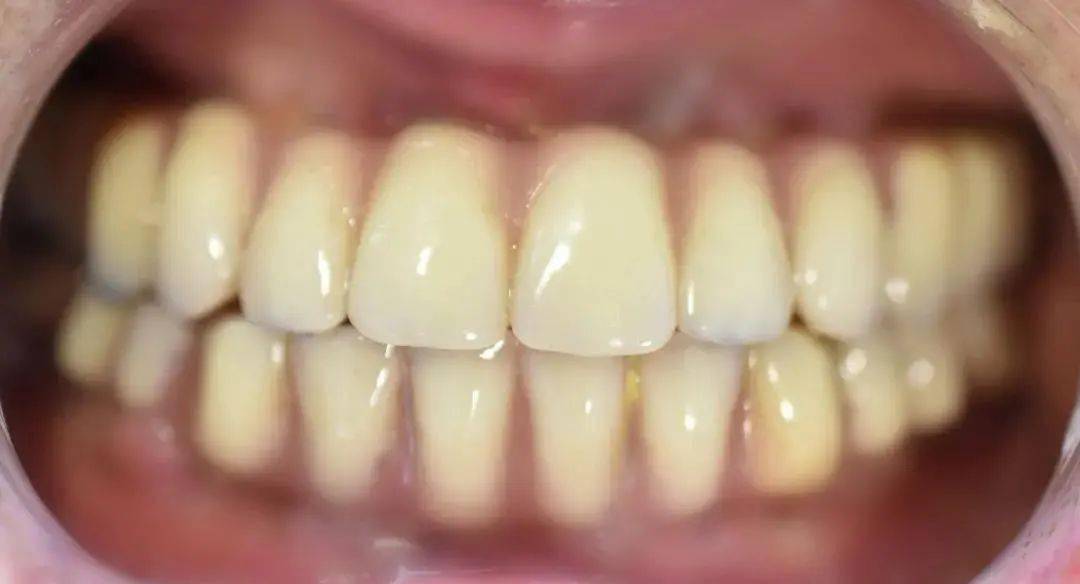

?种植牙前后口内照 , 左侧为戴牙前 , 右侧为戴牙后 。

文章图片